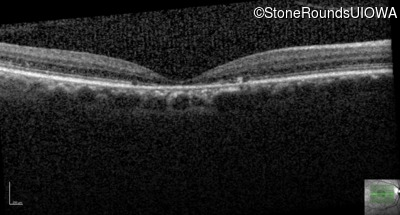

AR Stargardt Disease (IIA)

Age at visit: 54 years

This 54 year old woman first noticed reduced visual acuity in her mid 20's.

Diagnosis & molecular findings

Disease Gene Allele 1 variant(s) Allele 2 variant(s) Inheritance mode

AR Stargardt Disease ABCA4 Gly1961Glu GGA>GAA Cys2150Tyr TGT>TAT AR